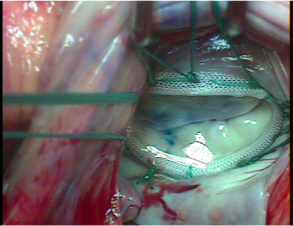

経カテーテル大動脈弁置換術 (TAVI)とは、狭くなった大動脈弁をバルーンで押し広げて、カテーテルという管を用いて折り畳んだ専用の生体弁を留置する治療法です。現在、足の血管からカテーテルを挿入する方法と左胸に小さな切開をおいて左心室からカテーテルを挿入する方法があります。

図4 経カテーテル大動脈弁置換術 (TAVI)で用いる生体弁

図5 経カテーテル大動脈弁置換術 (TAVI)